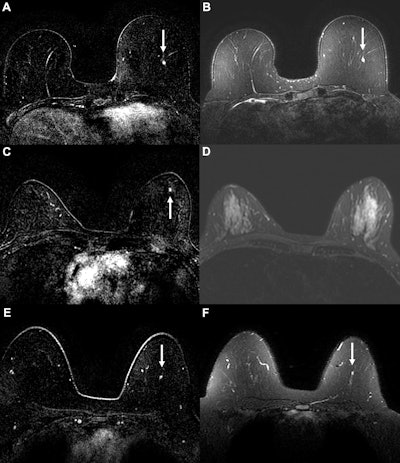

Example cancer examinations where the AI suspicion score prompted triage to abbreviated breast MRI, but readers still assessed the abbreviated MRI exam as suspicious. Axial (A) dynamic contrast-enhanced (DCE) and (B) fat-saturated T2-weighted MRI scans in a 58-year-old woman with a 0.3-cm enhancing focus (arrow) in the left breast. The AI tool generated a suspicion score of 0.68 (43rd percentile of suspicion score), prompting triage at the 50% threshold. For abbreviated MRI, readers gave the examination a suspicious assessment, but for the full MRI protocol, readers missed the suspicious finding, possibly owing to its T2 hyperintensity. The original radiologist also gave a benign assessment, but cancer was diagnosed six months later via mammography, with calcifications indicating ductal carcinoma in situ. Axial (C) DCE and (D) fat-saturated T2-weighted MRI scans in a 51-year-old woman with a 0.3-cm enhancing focus (arrow in C) in the left breast. The AI tool generated a suspicion score of 0.42 (17th percentile), prompting triage at the 50% threshold. For both abbreviated and full MRI, readers gave the examination a suspicious assessment, although the original radiologist report gave a benign assessment. Cancer was diagnosed six months later via mammography. Biopsied calcifications indicated ductal carcinoma in situ. Axial (E) DCE and (F) fat-saturated T2-weighted MRI scans in a 49-year-old woman with a 0.4-cm enhancing focus (arrow) in the left breast. The AI tool generated a suspicion score of 0.62 (37th percentile), prompting triage at the 50% threshold. The lesion was missed by readers at both abbreviated and full MRI. The patient was diagnosed with invasive ductal carcinoma six months after an abnormal contrast-enhanced mammogram.Example cancer examinations where the AI suspicion score prompted triage to abbreviated breast MRI, but readers still assessed the abbreviated MRI exam as suspicious. Axial (A) dynamic contrast-enhanced (DCE) and (B) fat-saturated T2-weighted MRI scans in a 58-year-old woman with a 0.3-cm enhancing focus (arrow) in the left breast. The AI tool generated a suspicion score of 0.68 (43rd percentile of suspicion score), prompting triage at the 50% threshold. For abbreviated MRI, readers gave the examination a suspicious assessment, but for the full MRI protocol, readers missed the suspicious finding, possibly owing to its T2 hyperintensity. The original radiologist also gave a benign assessment, but cancer was diagnosed six months later via mammography, with calcifications indicating ductal carcinoma in situ. Axial (C) DCE and (D) fat-saturated T2-weighted MRI scans in a 51-year-old woman with a 0.3-cm enhancing focus (arrow in C) in the left breast. The AI tool generated a suspicion score of 0.42 (17th percentile), prompting triage at the 50% threshold. For both abbreviated and full MRI, readers gave the examination a suspicious assessment, although the original radiologist report gave a benign assessment. Cancer was diagnosed six months later via mammography. Biopsied calcifications indicated ductal carcinoma in situ. Axial (E) DCE and (F) fat-saturated T2-weighted MRI scans in a 49-year-old woman with a 0.4-cm enhancing focus (arrow) in the left breast. The AI tool generated a suspicion score of 0.62 (37th percentile), prompting triage at the 50% threshold. The lesion was missed by readers at both abbreviated and full MRI. The patient was diagnosed with invasive ductal carcinoma six months after an abnormal contrast-enhanced mammogram.RSNA